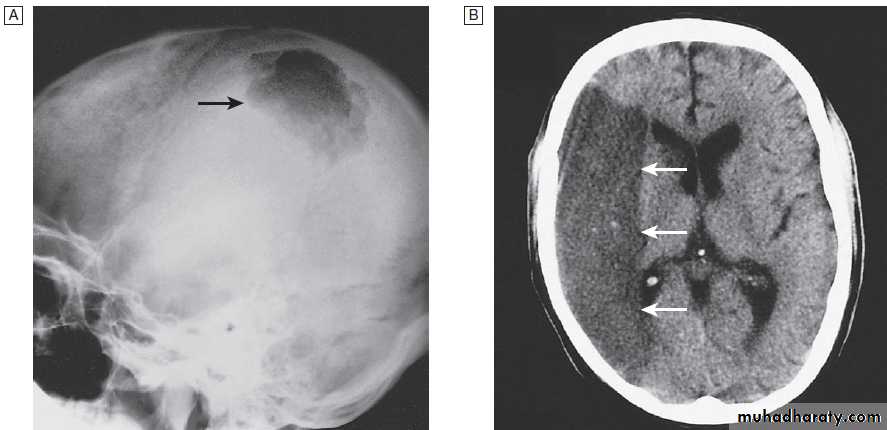

Fig. Different techniques of imaging the head and brain. A Skull X-ray showing lytic skull lesion (eosinophilic granuloma – arrow). B CT

showing complete middle cerebral artery infarct (arrows). C MRI showing widespread areas of high signal in multiple sclerosis (arrows). D SPECT after

caudate infarct showing relative hypoperfusion of overlying right cerebral cortex (arrows).